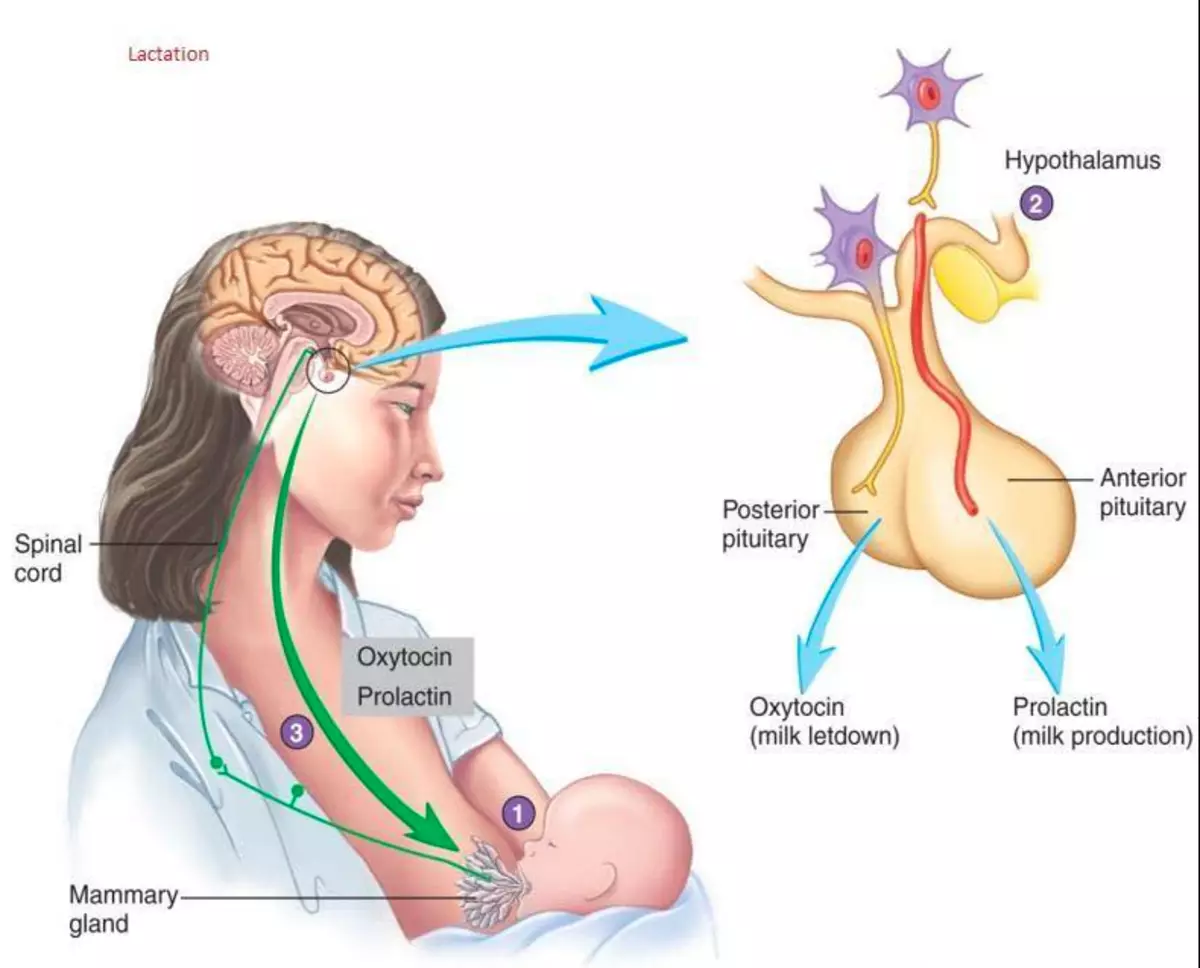

Как работает центр насыщения в гипоталамусе: визуальные иллюстрации